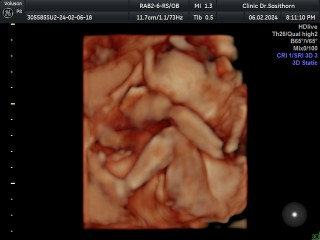

ทีมมิถุนา เป็นไงบ้างค่ะ บ้านนี้5เดือนเเล้วหมอบอกผู้หญิงเเต่ยังไม่เเน่ใจ100% น้องดิ้นเก่งมากจร้า เเต่ท้องแม่ยังไม่เลยค่ะไม่เหมือนคนท้องเลยจ้าแม่ๆ รูกสึกเจ็บจิมิมาก

บ้านนี้ก็5เดือนเหมือนกันเรยคะ ท้องออกเหมือนแค่เป็นคนอ้วนเชยๆเองคะแต่น้องตอดเก่งและแรงขึ้นคะ😂ทีมลูกสาวคะ นน.น้องเท่าไหร่แร้วคะ

ทีม มิ.ย ค่ะ ท้อง2 เป็นผู้ชาย ออกแค่ท้องค่ะ ตัวแม่เท่าเดิมเลยค่ะ😆ดิ้นเก่งเป็นเวลา แม่ไม่มีอาการเจ็บปวดอะไร แค่ตึงท้อง สบายมากเลยค่ะ

ทีมมิถุนายนเหมือนกันอีกไม่กี่วันจะครบ6เดือนแล้วบ้านนี้ท้องออกเหมือนคนอ้วนเฉยๆค่ะ🤣🤣 ทีมลูกสาวค่ะ

บ้านนี้ 5เดือนกว่าจะ6เดือนจ้า ผู้ชาย ท้องใหญ่มาก น้ำหนักขึ้นมา 5โล ปวดขา ปวดขาหนีบ มากจ้า

ทีมมิถุนาเหมือนกันค่ะแม่ หมอบอกผช.100% แข็งแรง ดิ้นเก่งถีบแม่เก่งมากค่ะ ปวดขา ปวดหลังมากค่ะ

มิถุนายน เหมือนกันค่ะ หมอบอกว่าผช.แต่ยังไม่100%คุณลุงหมอบอกแข็งแรงดิ้นเก่ง

บ้านนี้ไปซาร์ดมาเมื่อวานคะ ผู้ชาย 5เดือน ท้องออกแล้วคะ